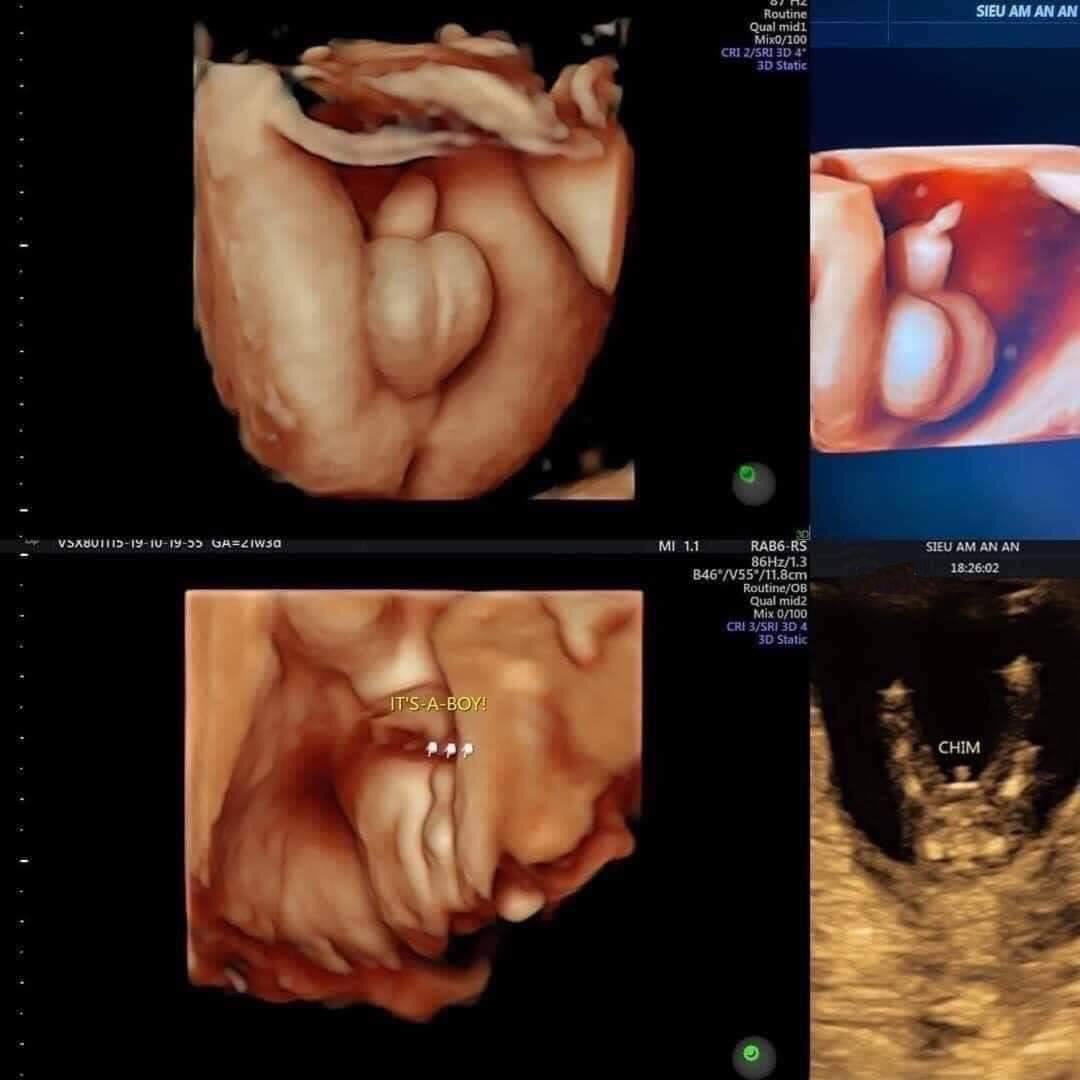

Một số biện pháp hiệu quả để biết mang thai trai hay gái đó là sử dụng máy siêu âm có độ phân giản cao, có thể phân biệt được trai hay gái lúc 11-13 tuần, xem thêm siêu âm đo độ mờ da gáy

Hiện nay phòng khám bác sỹ Nguyễn Đức TỈnh với đội ngũ bác sỹ chuyên sâu về siêu âm thai và quản lý thai kỳ. đặc biệt phòng khám được trang bị hệ thống máy móc hiện đại như máy siêu âm thai 5D mang lại hình ảnh rõ nét, chẩn đoán sớm các dị tật bất thường thai nhi.